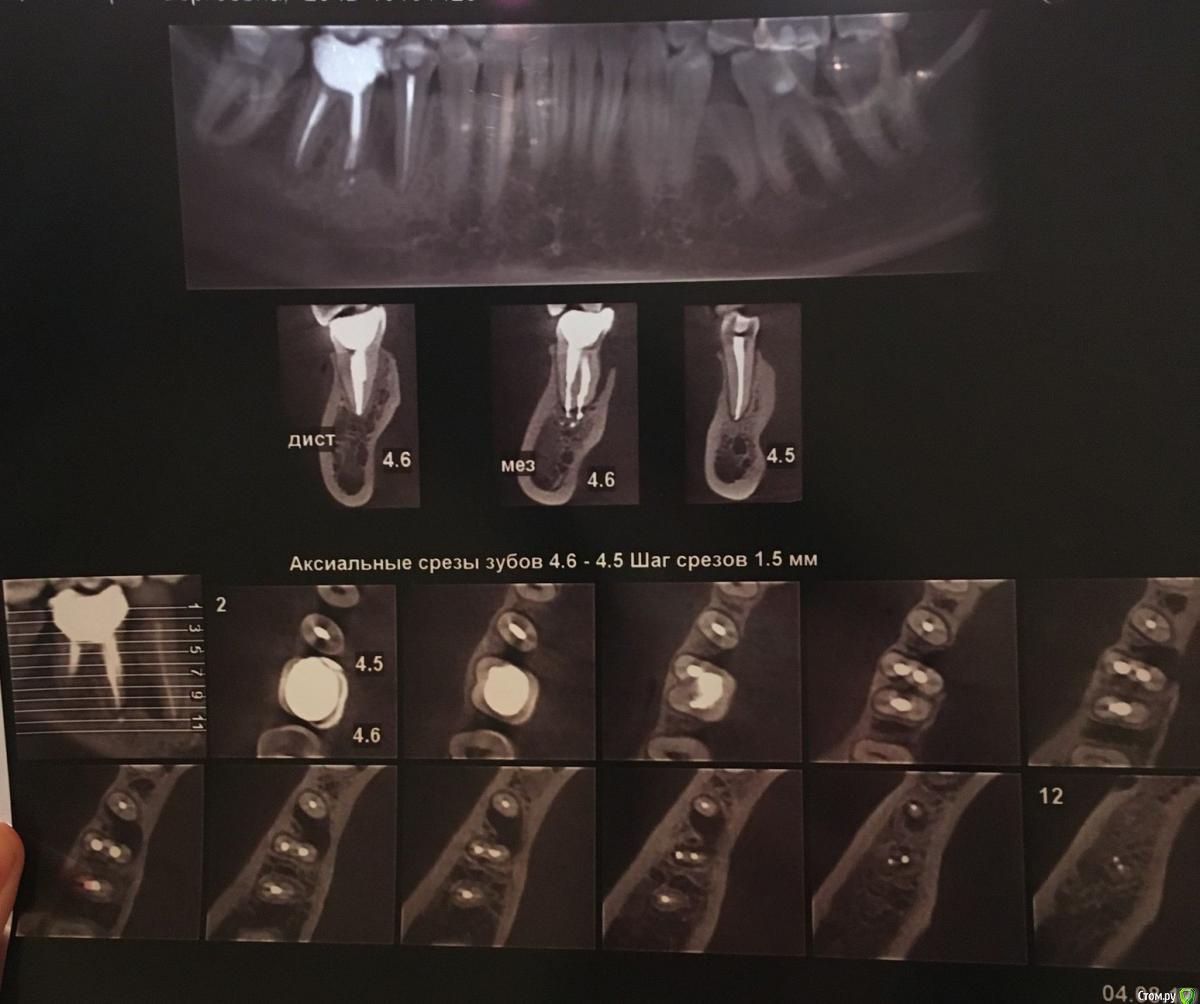

Volha Опубликовано 27 сентября, 2017 Поделиться Опубликовано 27 сентября, 2017 Посоветуйте, что делать с зубами. Здравствуйте!Нужна помощь. После лечения пульпита у премоляра, появился гнойник на десне (с внутренней стороны). На последнем сделанном снимке, помимо имеющегося воспаления, видно воспаление у корней 47 зуба. Врач предположил, что это все может быть трещина корня и нужно перелечивать все каналы под микроскопом. При этом нет никаких гарантий что это поможет. Есть вероятность того, что после всего проделанного лечения эти зубы придется удалять. Может есть другой вариант как это исправить? Судя по ценам, как я понимаю, выдернуть эти зубы и вставить импланты выйдет не слишком дороже лечения. P.s Посмотрев снимки, увидела что у меня действительно "убогий прикус" =). Буду признательна советам как это можно исправить. Ссылка на комментарий

DmitrySH Опубликовано 28 сентября, 2017 Поделиться Опубликовано 28 сентября, 2017 видно воспаление у корней 47 зуба. Нет. Только 45,46 Ссылка на комментарий

Volha Опубликовано 28 сентября, 2017 Автор Поделиться Опубликовано 28 сентября, 2017 Нет. Только 45,46 Не исключаю, что могла перепутать. Два рядом стоящих зуба, маляр и премоляр. Ссылка на комментарий